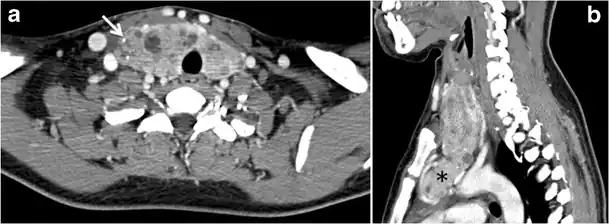

Fig. 13. A 27-year-old female patient known to have goiter. a, b Axial and sagittal enhanced CT scan images of the neck demonstrate a heterogeneously enhancing, enlarged thyroid gland with scattered calcifications (white arrow), cystic changes, and substantial retro-sternal extension (black asterisks). No lymphadenopathy or substantial airway narrowing.[1]

Malignancy can coexist within the goiter and a CT scan may give a clue if there are abnormal cervical lymph nodes and/or signs of invasion. Retrosternal extension (Fig. 15) could affect the surgical approach, as a lower extent may require a partial or total sternotomy to facilitate complete resection. Therefore, the distance of the retrosternal extent from the sternal notch should be measured on a sagittal image.[1]